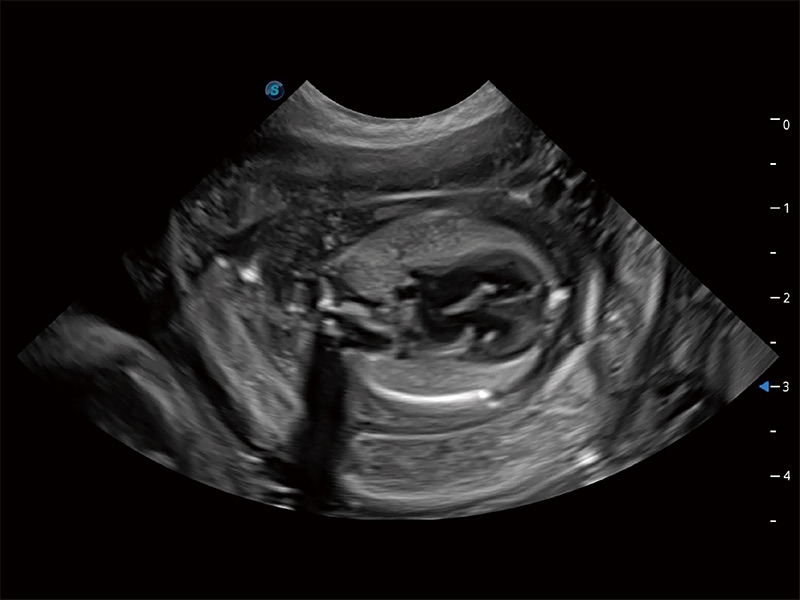

ProPet 80 配备了丰富的心脏探头群、先进的成像技术和专业的心脏测量工具,可帮助动物医生为不同体型和生理结构的动物提供心脏和心肌功能的全面评估。

ProPet 80 专为动物医生设计,对不同的动物体型和生理结构作出了针对性的优化。通过动物影像专用软件,可满足个性化的应用需求,帮助动物医生获得更精确的诊断数据。

为精细结构及组织边缘提供高清晰度的图像和更大的成像视野。帮助减轻医生的用眼疲劳,快速精准获得测量的数据。

ProPet 80 全新的动物超声智能软件和丰富的探头群,为动物医生提供了高清晰度和精细分辨率的图像,无论在宠物、马科、畜牧还是实验室动物等应用中都可以轻松应对,为您的日常工作带来满意的体验。